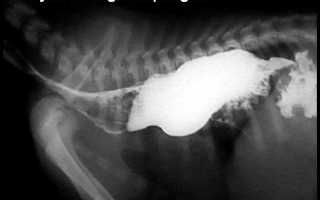

Диагноз ставят по результатам рентгенографии. Простая рентгенография обычно выявляет расширение грудного отдела пищевода и часто заполнение желудка воздухом. Глотание бария (твердый корм в оболочке из сульфата бария) является весьма эффективным методом подтверждения задержки пищи в пищеводе. Обычно расширение происходит в грудном отделе пищевода, поскольку способность к расширению там больше, чем в шейной области, хотя можно наблюдать расширение и шейного отдела пищевода, особенно у кошек. Флюороскопия помогает подтвердить нарушение перистальтики, а также отсутствие другого заболевания пищевода. Пище редко удается попадать в желудок, и может наблюдаться конусовидное сужение дистального отдела пищевода в непосредственной близости к желудку. Это результат нормальной функции дистального сфинктера.

Рисунок 1 — Рентгенограмма собаки с мегаэзофагусом